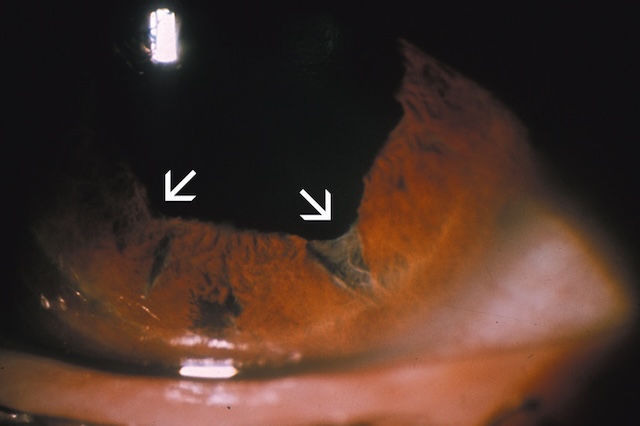

- • une iridodialyse : désinsertion de la base de l’iris (fig. 11.4);

Fig. 11.4 Iridodialyse post-traumatique inférieure (A) et supérieure (B). L’image A montre une iridodialyse inférieure post-traumatique : un décollement net de l’insertion de l’iris est visible en bas de la chambre antérieure, formant une seconde pupille apparente qui laisse passer la lumière en zone déclive. La cornée est claire, et l’examen met en évidence une double ouverture pupillaire. L’image B montre une iridodialyse supérieure. L’iris est déformé vers le haut avec un aspect festonné, tandis que la conjonctive sus-jacente est injectée, traduisant un état inflammatoire. Dans les deux cas, la perte d’ancrage irien modifie la forme de la pupille et peut s’accompagner de photophobie ou de troubles visuels.